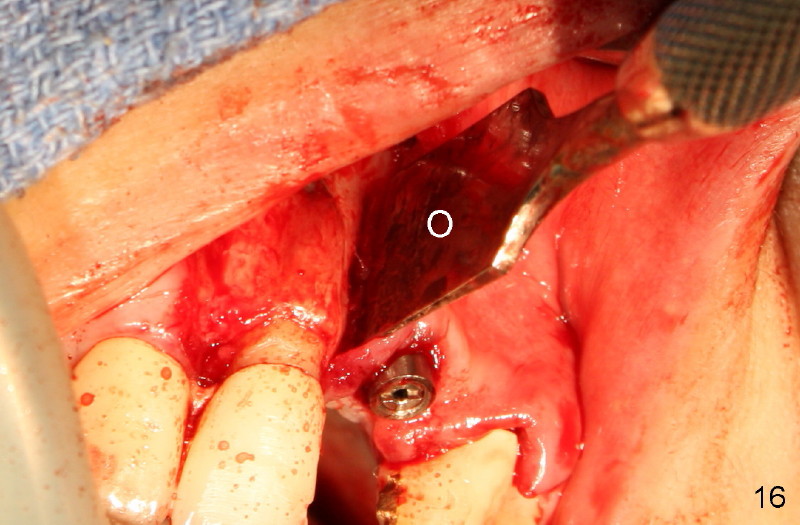

Segmental Osteotomy for Misplaced Implant

This corrective surgery was performed by Dr. Bernee Dunson.

Xin Wei, DDS, PhD, MS 1st edition 12/21/2011, last revision 12/23/2011